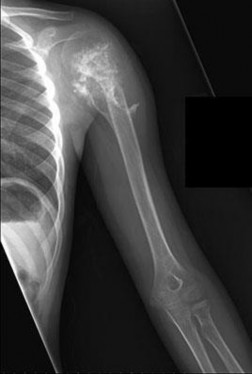

Question 12

A 13-year-old elite baseball pitcher presents with vague, insidious onset shoulder pain that is worst during the deceleration phase of throwing. He denies any acute pop or trauma. Radiographs reveal widening and lateral fragmentation of the proximal humeral physis compared to the contralateral shoulder. What is the most appropriate initial management?

Explanation

The patient is presenting with 'Little League Shoulder,' which is proximal humeral epiphysiolysis. It is an overuse injury caused by repetitive rotational stress on the open physis during the throwing motion. The mainstay of treatment is absolute rest from throwing, typically for 3 months, or until the patient is completely pain-free and radiographs show healing of the physis. Once healed, a gradual return-to-throw program focusing on pitching mechanics is initiated.